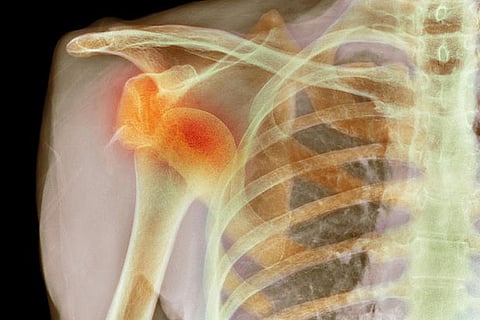

When the joint repeatedly slips out of place it leads to chronic shoulder instability. Reasons for the condition can vary from severe injury, fall or trauma, overuse of the joint to genetic disorders that cause joint loosening. Although more common amongst sports persons, the condition can affect anyone whose shoulder dislocation is not treated properly.

In severe cases, it can also result in visible deformity leading to a compromised quality of life. Therefore, it is important to consult an orthopedist who can help with accurate diagnosis through physical examination of the shoulder joint and an X-ray or MRI.